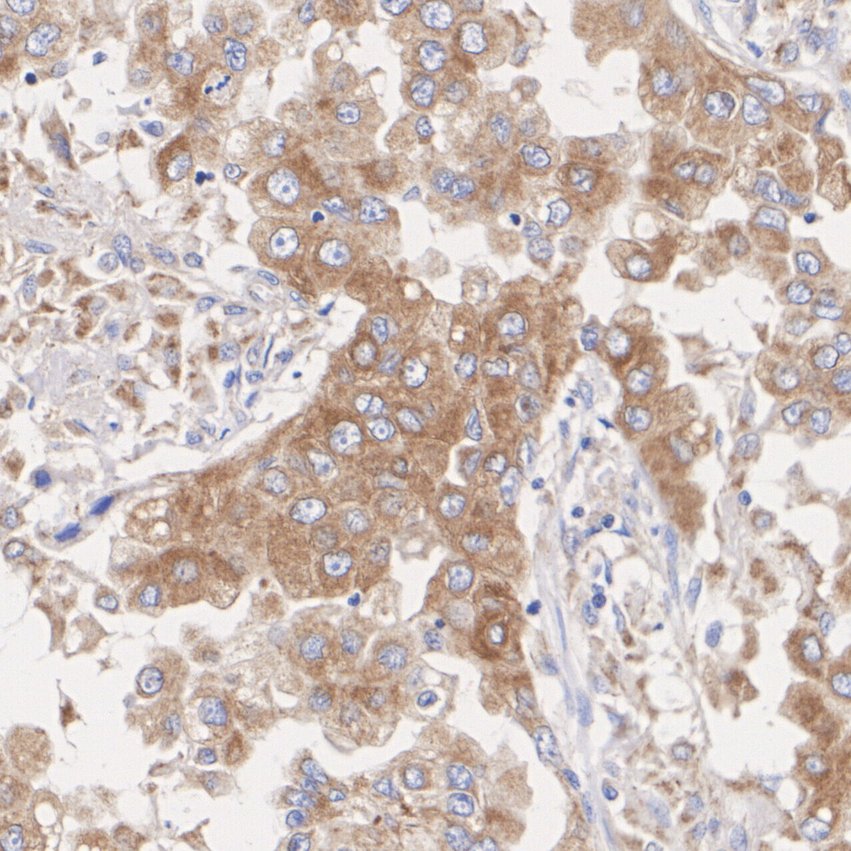

ET1610-93_5.jpg Fig5: Immunohistochemical analysis of paraffin-embedded human colon carcinoma tissue with Rabbit anti-NLRP3 antibody (ET1610-93) at 1/400 dilution.

The section was pre-treated using heat mediated antigen retrieval with sodium citrate buffer (pH 6.0) (high pressure) for 2 minutes. The tissues were blocked in 1% BSA for 20 minutes at room temperature, washed with ddH2O and PBS, and then probed with the primary antibody (ET1610-93) at 1/400 dilution for 1 hour at room temperature. The detection was performed using an HRP conjugated compact polymer system. DAB was used as the chromogen. Tissues were counterstained with hematoxylin and mounted with DPX.